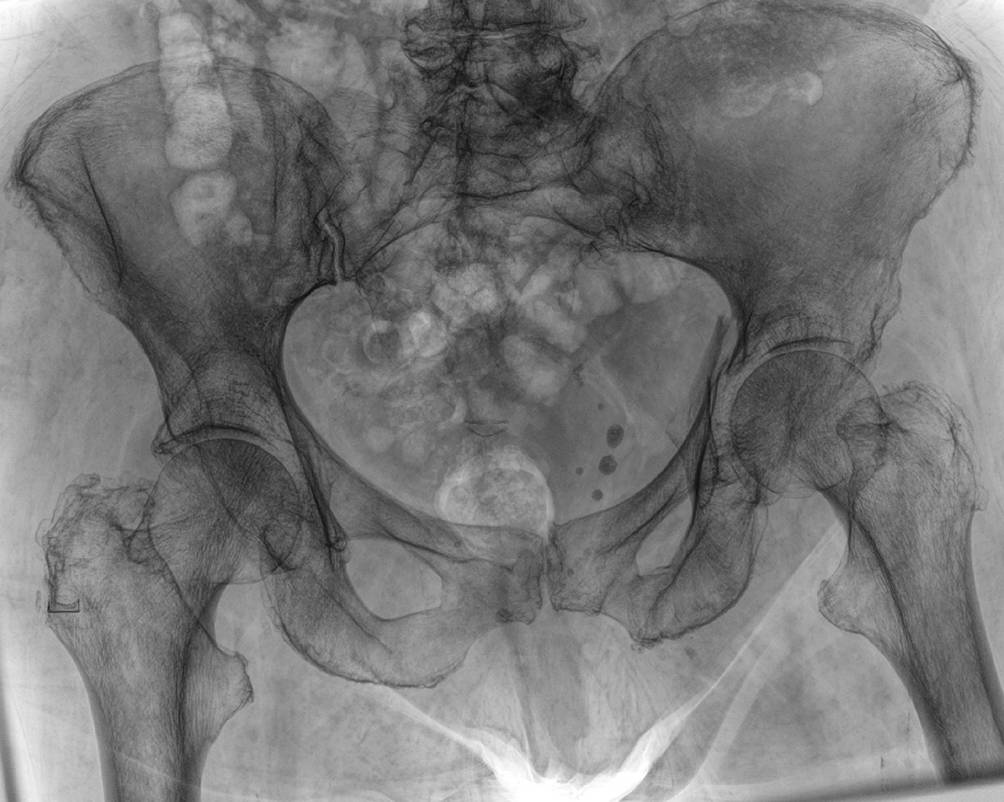

• Eine Röntgendiagnostik mit Beckenübersichts‑, Ala- und Obturatoraufnahme kann initial durchgeführt werden, spielt hinsichtlich der Planung der minimal-invasiven, navigierten Versorgung jedoch nur eine untergeordnete Rolle (Abb. 1).

Abb. 1

Die initiale Röntgendiagnostik kann zwar einen Hinweis auf Frakturen im Becken geben, ist jedoch für die Therapieplanung allein nicht ausreichend. Hier zeigt sich eine Azetabulumfraktur auf der linken Seite einer 89-jährigen Frau nach häuslichem Sturz, die genaue Frakturmorphologie kann jedoch nur bedingt festgestellt werden